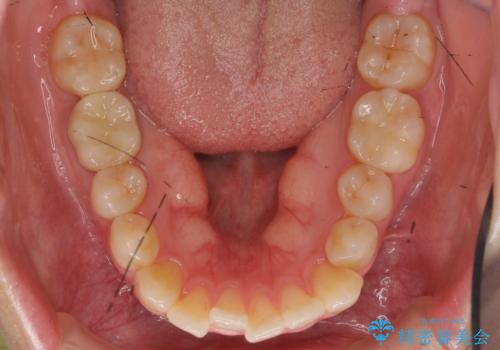

- 前歯のがたつきをきにされていました。

上下の前歯をやすりがけする処置(IPR)を行い、前歯の並びを出っ歯にしないようにしながら整えました。